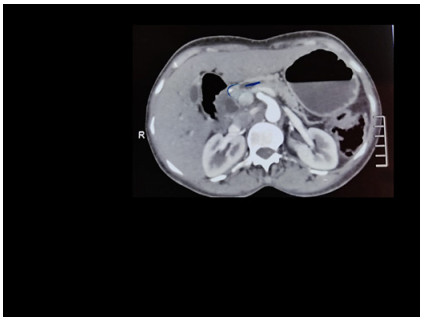

Abstract: Pancreatic adeno-mixed neuroendocrine non-endocrine (pMINEN) tumors are extremely rare [Pancreatology. 2021;21(1):224–235]. They are known to have distal metastasis at presentation and have a comparatively lower survival rate than similar staged neuroendocrine (NEN) carcinoma, adenocarcinoma, and small-cell lung tumor from which its treatment patterns are extrapolated. Also, very less is known about its molecular structure and natural courses. There is a dearth of data about pMINEN in the literature, and also there is a lack of large multicentral trials due to which the MINEN tumors do not have a standard universal management protocol. We discuss here the clinical dilemmas that arise during diagnosis and reporting and urge to form a multicentric trial to formulate a focused protocolized approach. We describe here our encounter with a pancreatic head lesion which on immunohistochemical analysis turned out to be a pMINEN with moderately differentiating ductal adenocarcinoma and low-grade NEN tumor. Radical R0 surgery with multimodal treatment (chemotherapy + radiotherapy) gains improved survival in long term.